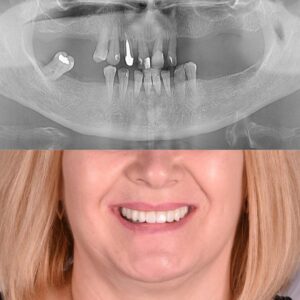

Rezultatul final

Rezultatul obținut a fost o reabilitare orală completă, stabilă și funcțională:

Pacienta a trecut de la imposibilitatea de a mușca un măr, la o funcție orală complet normală

Cazul demonstrează că parodontoza avansată nu este un capăt de drum, ci un punct de plecare pentru o soluție modernă, sigură și predictibilă.

Prin tehnologia All-on-X, planificare digitală și abordare interdisciplinară, este posibilă obținerea unei reabilitări orale complete, stabile și durabile, chiar și în cazuri clinice complexe.